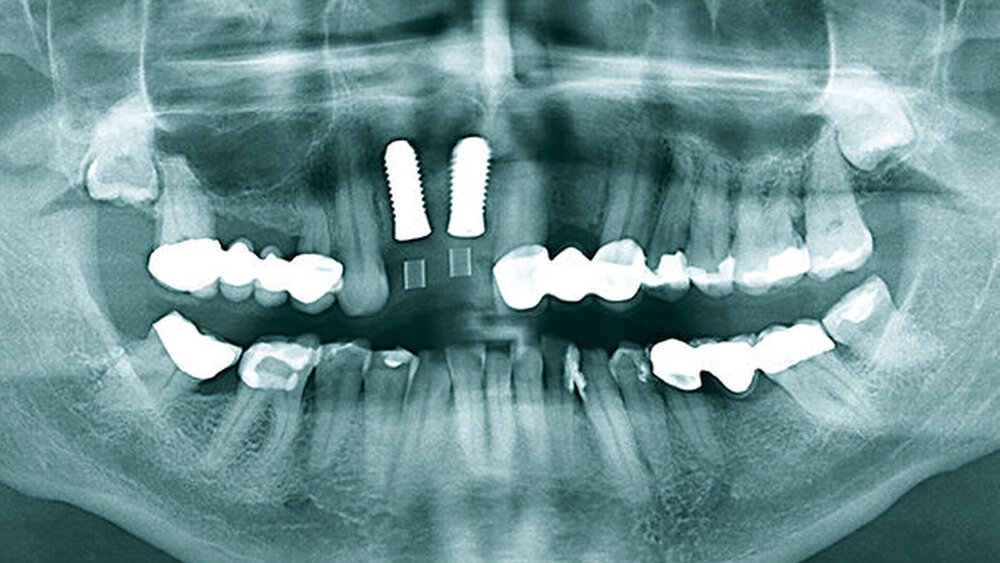

Nach Extraktion wurzelbehandelter Zähne liegt häufig ein horizontaler Kieferknochendefekt vor; die vestibuläre Knochenlamelle fehlt partiell oder vollständig. Das OPG (Abb. 3) zeigte genügend vertikales Knochenangebot, die lückenbegrenzenden Zähne und Parodontien waren vital. Die bidigitale Palpation bestätigte den Verdacht auf eine bestehende vestibuläre Defektgeometrie. Die chirurgischen Konzepte positiv unterstützend, lag ein dicker Gingiva-Biotyp vor. Der Restzahnbestand und parodontale Screening-Index (PSI) waren unauffällig.

Geplant wurden zwei zweiteilige Hexalobe-Implantate mit dem Durchmesser von 4,0 mm, Länge 12 mm. Die Implantate sollten mit begleitender GBR inseriert werden und anschließend gedeckt einheilen. Das setzte die Wahl eines zweiteiligen Keramikimplantats voraus. Im Vorfeld des chirurgischen Eingriffs wurde eine Mess- und Bohrschablone konventionell nach prothetischem Wax-up für die prothetisch orientierte Implantatinsertion angefertigt.

Die Implantatschulter wurde leicht supracrestal platziert, sodass die prothetische Plattform zirka 2 mm unter dem Weichgewebeniveau zu liegen kam (Abb. 5). Lateral der Implantatschulter wurden die autologen Knochenspäne gemischt mit feinkörnigem BioOss (Geistlich) eingebracht und die Implantate über den Klickmechanismus in der Innenkonfiguration des Implantats mit der PEEK-Abdeckkappe verschlossen (Abb. 6). Die CERALOG Hexalobe-Implantate sind im Halsbereich weniger rau als im enossalen Bereich, damit sich das Weichgewebe im Bereich des Implantathalses und die Knochenzellen an der mikrorauen Struktur im enossalen Bereich optimal anlagern können. Das Augmentat wurde mit einer Bio-Gide-Membran (Geistlich) abgedeckt. Es lag ausreichend keratinisierte Gingiva vor, sodass keine Weichgewebeverdickung erforderlich war. Der Wundverschluss erfolgte ohne Periostschlitzung (Abb. 7), um die Ernährungsphysiologie des Weichgewebes nicht zu verschlechtern und eine Verschiebung der Mukogingivalgrenzlinie nach koronal zu vermeiden. Der Lappen ließ sich für den spannungsfreien Wundverschluss tunnelierend ausreichend weit nach subnasal präparieren. Im Anschluss an die Implantatinsertion wurde die Valplast-Prothese basal ausgeschliffen, um augmentationsbedingte Druckstellen zu vermeiden. Die postoperative Röntgenkontrolle (Abb. 8) zeigt eine anatomisch exakte Implantatpositionierung nach Schablonenvorgabe.

Während der komplikationslosen Heilungsphase betreute der Hauszahnarzt den Patienten. Wie geplant, erfolgte nach zwölf Wochen die Implantatfreilegung (Abb. 9) in unserer Praxis. Das Weichgewebe zeigte sich in einem blutungs- und reizfreien Zustand. Mit einer leicht palatinal orientierten crestalen Kieferkammschnittführung wurden die Implantate freigelegt, das Weichgewebe wurde nach vestibulär verdrängt (Abb. 10) und die Gingivaformer wurden aufgesetzt. Um einen quantitativen Zugewinn von keratinisiertem Gewebe zu erhalten, wurde die Naht zwischen den Implantaten nicht komplett geschlossen. Die Implantate zeigten sich klinisch und röntgenologisch sicher osseointegriert (Abb. 11).